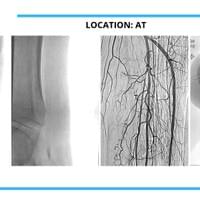

The cases below show the DABRA Catheter navigating the vessels without the aid of a guidewire.

The cases below show the DABRA Catheter navigating the vessel alongside a guidewire without disrupting it. The guidewire is NOT aiding the DABRA Catheter in navigation, rather it's maintaining real estate already gained by DABRA in a previous pass through the vessel so the DABRA Catheter can increase lumenal gain.

These methods worked. Again, proof is a 94% success rate with NO adverse events in their FDA study. Throughout the study, the technology worked on 60 out of 64 patients! It recanalized 75 out of 83 lesions (100% blockages) that could not be crossed with a standard guidewire. Every vessel in the legs was represented in the study, both above- and below-the-knee. And multiple approaches were used from the most typical contralateral cross-over technique to tibial access or from the dorsalis pedis. Those results were not typical with comparative devices.